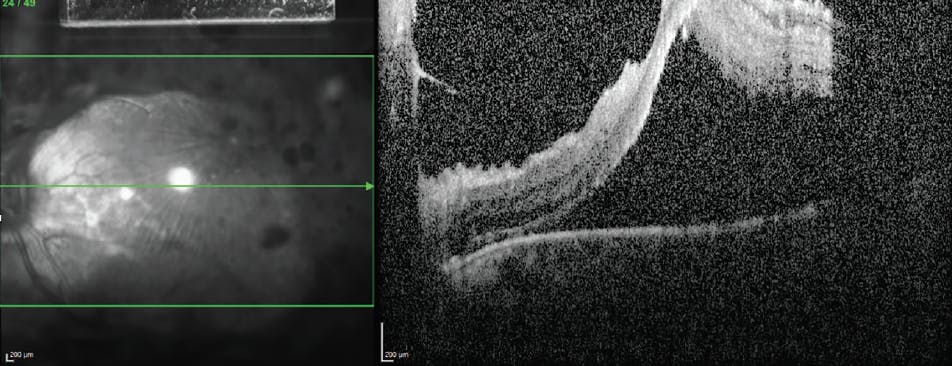

<p>Figure. This 27-year-old woman with type 1 diabetes presented with recent onset vision loss in her left eye. She had noticed floaters for a couple of months but did not present to the clinic until her vision had decreased. On examination, VA was 20/400 with extensive tractional membranes inducing a fovea-off macular detachment. Ultimately, she required pars plana vitrectomy with extensive membrane segmentation and delamination to reattach her retina with 20/400 vision under silicone oil. The right eye received full PRP along with anti-VEGF therapy for treatment of PDR.</p>

Figure. This 27-year-old woman with type 1 diabetes presented with recent onset vision loss in her left eye. She had noticed floaters for a couple of months but did not present to the clinic until her vision had decreased. On examination, VA was 20/400 with extensive tractional membranes inducing a fovea-off macular detachment. Ultimately, she required pars plana vitrectomy with extensive membrane segmentation and delamination to reattach her retina with 20/400 vision under silicone oil. The right eye received full PRP along with anti-VEGF therapy for treatment of PDR.